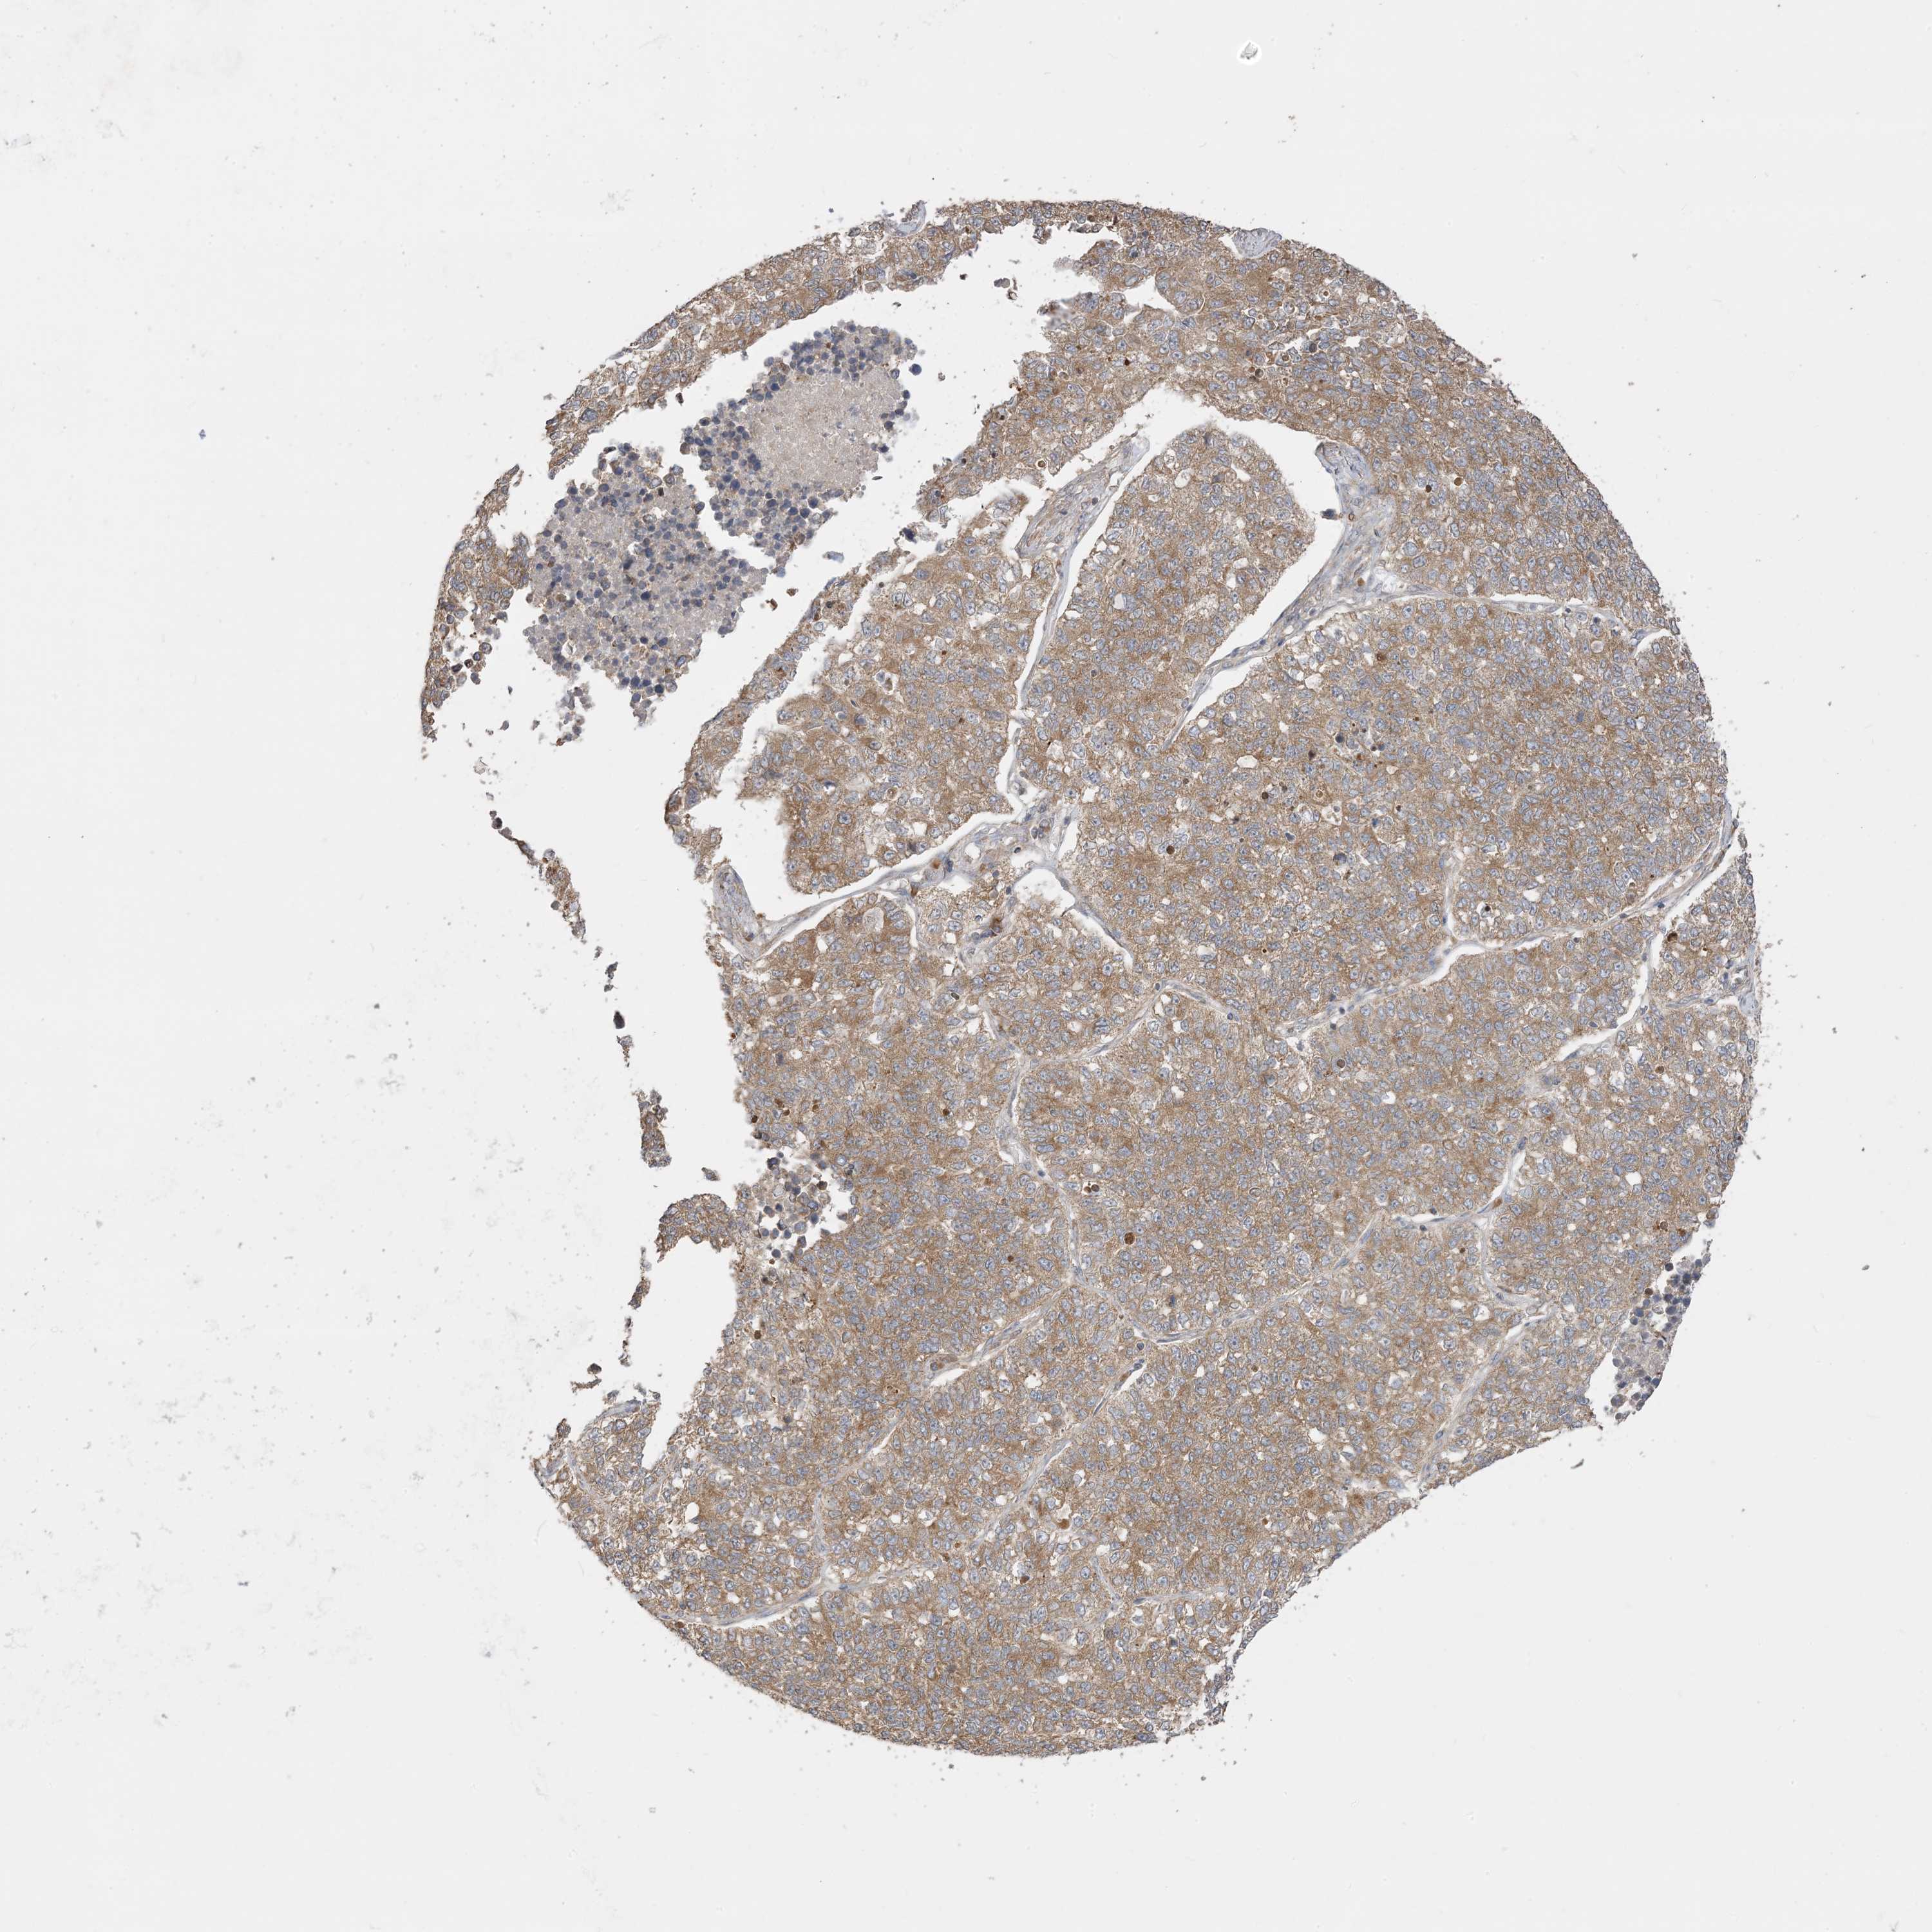

LUNG ADENOCARCINOMA (VALIDATION) - Interactive survival scatter ploti

The Survival Scatter plot shows the clinical status (i.e. dead or alive) for all individuals in the patient cohort, based on the same data that underlies the corresponding Kaplan-Meier plots. Patients that are alive at last time for follow-up are shown in blue and patients who have died during the study are shown in red.

The x-axis shows the expression levels (FPKM) of the investigated gene in the tumor tissue at the time of diagnosis. The y-axis shows the follow-up time after diagnosis (years). Both axes are complimented with kernel density curves demonstrating the data density over the axes. The top density plot shows the expression levels (FPKM) distribution among dead (red) and alive patients (blue). The right density plot shows the data density of the survived years of dead patients with high and low expression levels respectively, stratified using the cutoff indicated by the vertical dashed line through the Survival Scatter plot. This cutoff is automatically defined based on the FPKM cutoff that minimizes the p-score. The cutoff can be changed by dragging the vertical line or by entering a cutoff value in the square labeled "Current cut-off".

Under the Survival Scatter plot the p-score landscape (black curve; left axis) is shown together with dead median separation (red curve; right axis). Dead median separation is the difference in median mRNA expression between patients who have died with high and low expression, respectively. It is calculated as follows: median FPKM expression of dead patients with high expression - median FPKM expression of dead patients with low expression. This is intended to aid the user in visually exploring custom cutoffs and the associated p-scores and dead median separation.

Individual patient data is displayed and can be filtered by clicking on one or more of the category buttons on the top of the page. Categories describing expression level and patient information include: high, low, alive, dead, female, male and tumor stages. The scale of the x-axis can be toggled between linear and log-scale by clicking on the "x log" button. Mouse-over function shows TCGA ID, patient information and mRNA expression (FPKM) for each patient.

& Survival analysisi

Kaplan-Meier plots summarize results from analysis of correlation between mRNA expression level and patient survival. Patients were divided based on level of expression into one of the two groups "low" (under cut off) or "high" (over cut off). X-axis shows time for survival (years) and y-axis shows the probability of survival, where 1.0 corresponds to 100 percent.

SIRT3 is not prognostic in Lung Adenocarcinoma (validation)

Best expression cut offi

Based on the FPKM value of each gene, patients were classified into two groups and association between prognosis (survival) and gene expression (FPKM) was examined. The best expression cut-off refers the FPKM value that yields maximal difference with regard to survival between the two groups at the lowest log-rank P-value. Best expression cut-off was selected based on survival analysis .

When clicking on this number, the vertical dashed line indicating cut-off, the interactive survival plot, and the Kaplan-Meier curve will be adjusted to show results based on the best expression cut-off.

: 11.28

Average pTPM 15.9

Number of samples 105